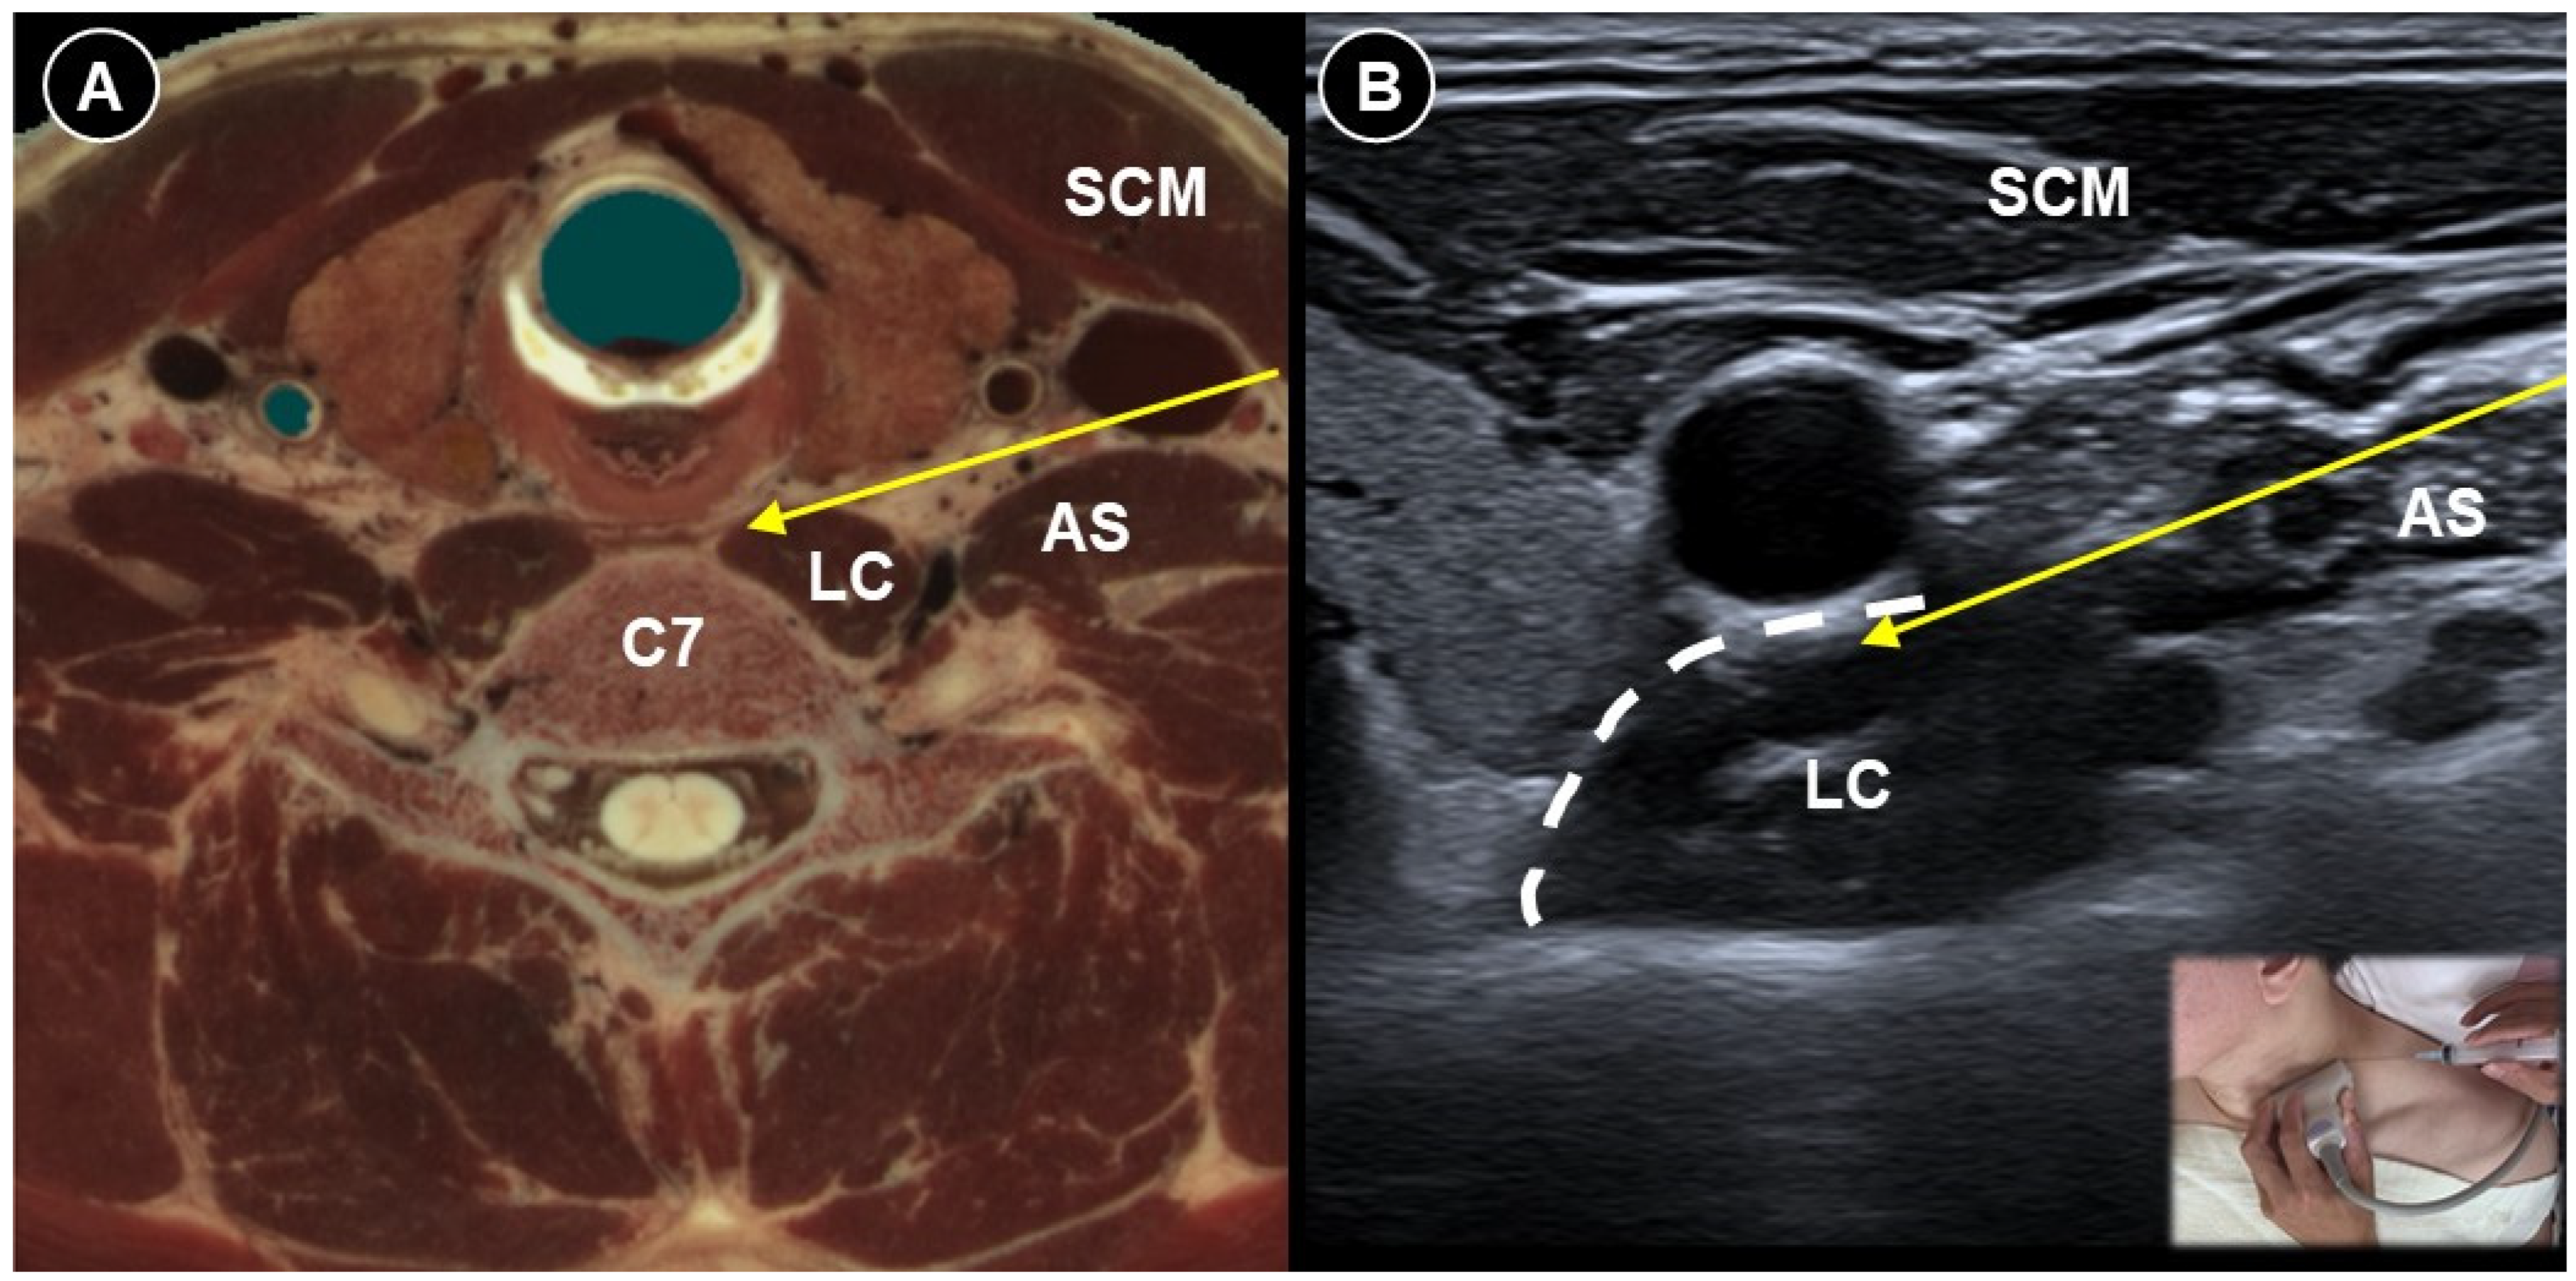

- Chang, K.-V.; Lin, C.-P.; Wu, W.-T.; Özçakar, L. Ultrasound-Guided Selective Cervical Root Injection for Postherpetic Neuralgia. Am. J. Phys. Med. Rehabil. 2017, 96, e189–e190. [Google Scholar] [CrossRef]

| Acute herpes pain | Burning, stabbing, or itching pain in the affected dermatomal distribution | Reactivation of VZV leading to viral nerve damage and inflammation | Cervical: supine, head turned to contralateral side Thoracic: prone | Cervical: